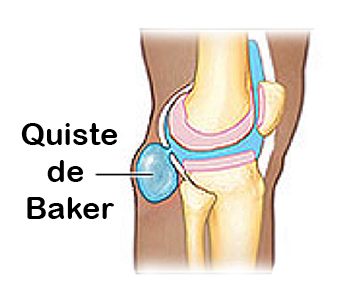

Nos especializamos en brindar tratamiento a las personas que parecen de Quiste de Baker o quiste poplíteo siendo una formación de contenido sinovial producida al debilitarse la membrana sinovial que recubre la articulación de la rodilla.

Nos especializamos en brindar tratamiento a las personas que parecen de Quiste de Baker o quiste poplíteo siendo una formación de contenido sinovial producida al debilitarse la membrana sinovial que recubre la articulación de la rodilla.

Este líquido sinovial se acumula en la bursa o bolsa del gastrocnemio-semimembranosa que se comunica con la articulación de la rodilla por una abertura en la superficie posterior y medial de la cápsula articular. El quiste de Baker puede aparecer a cualquier edad incluyendo las etapas tempranas de la vida.